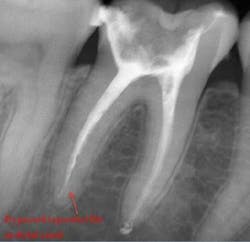

Using a pumping motion and adding additional sealer ensures that voids within the canals get filled. This generates the “puff” effect with small amount of sealer being extruded from the apex of canals. It also helps ensure accessory canals are not left unfilled.

If a file separates, take a P.A. film immediately to figure out where in the canal the file is lodged. Most likely there’s a curve that the file could not negotiate. Start negotiating the canal with a 6 or 8 C-file. The goal is to engage the space around the file where you can instrument next to it. It could take an extra 30 or 40 minutes and lots of irrigation, but you should be able to negotiate the canal with a 15 file to working length. Irrigate very well and obturate. Sometimes the file will actually exit the orifice of the tooth when irrigating. But it’s perfectly reasonable to use the file as part of the fill.